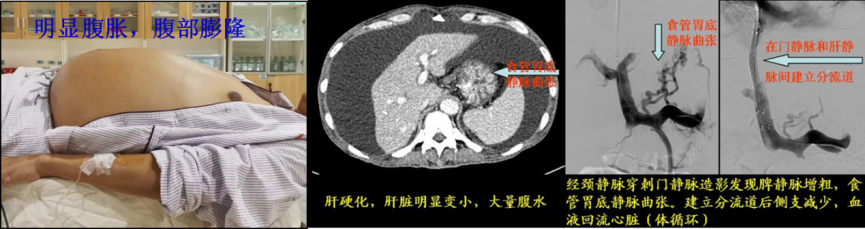

肝硬化門靜脈高壓癥(頑固性腹水和消化道出血)的介入治療

蘇老伯,61歲,患慢性乙肝、肝硬化多年,反復(fù)因嘔血、便血和腹脹(腹水)多次在我院住院。既往多次行“食道靜脈曲張?zhí)自g(shù)+胃底靜脈曲張硬化術(shù)”。近期因再次出現(xiàn)大量嘔血和腹脹前來(lái)我院住院,CT檢查發(fā)現(xiàn)“肝硬化、脾大、食管下段及胃底區(qū)靜脈曲張,大量腹水”。我科確診肝硬化門靜脈高壓癥,并成功進(jìn)行介入治療,術(shù)后患者未再出現(xiàn)嘔血,腹水明顯消退。